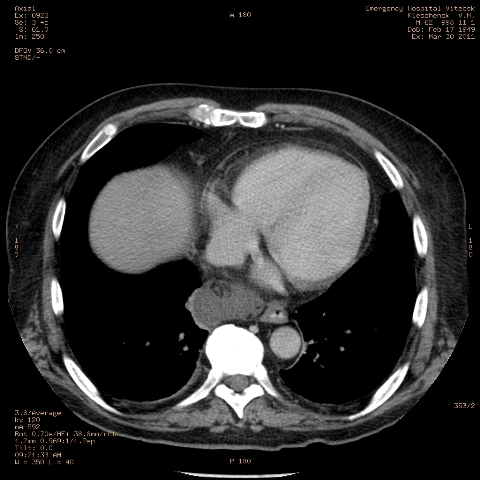

при исследовании органов брюшной полости по поводу абсцесса печени, в нижнем этаже средостения выявлено образование неоднородной плотности (-5-+25), при в/в контрастировании - не контрастируется, при per os - затёков из пищевода нет, неправильно овальной формы. предположительно киста перикарда? спасибо за помощь!

Может быть enteric duplication cyst. Как бы есть грыжа жира hiatal. И что с печенью? Мало срезов.